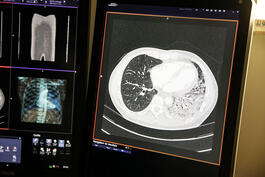

Saint Dié des Vosges hospital. A CT image showing the lungs of a patient with COVID-19. On the left in black the healthy lung, on the right the lung infected by the virus.

The Grand-Est region is one of the areas most affected by the pandemic.